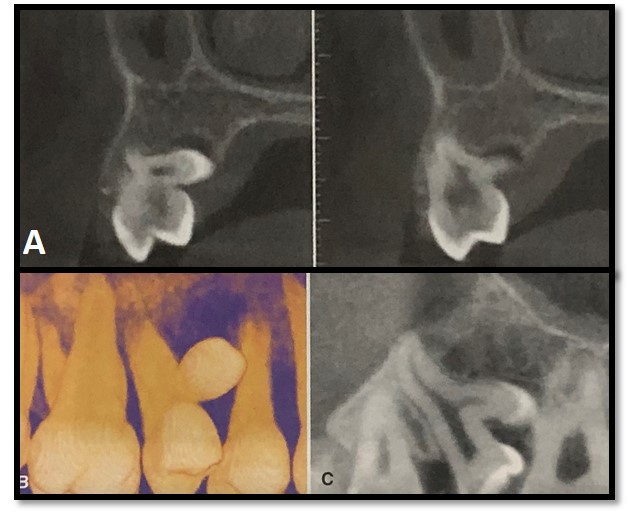

As radiografias são exames essenciais no diagnóstico destas anomalias de desenvolvimento dental (forma) pois permitem observar melhor a extensão da união e a presença dos condutos radiculares e raízes e orientar o tratamento.

Assim, permitem a segurança ao orientar o profissional quanto ao tratamento específico do dente, juntamente com o exame clínico. Trago pra vocês um caso não tão comum de fusão de molares (Figura 3, A e B). Observem atentamente a imagem. Neste caso o diagnóstico diferencial da fusão incluem: geminação e macrodontia.

Veja outros exemplos na prática